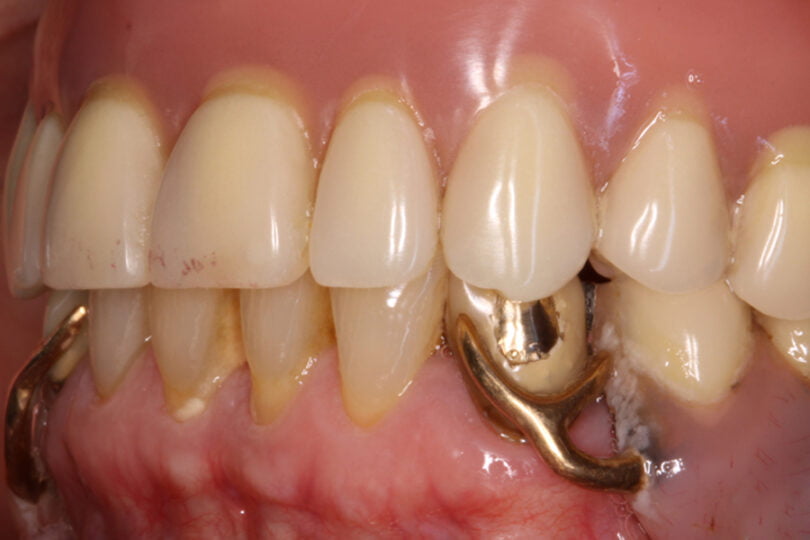

As seguintes imagens apresentam um dos casos incluídos no estudo (figura 03 – 15).